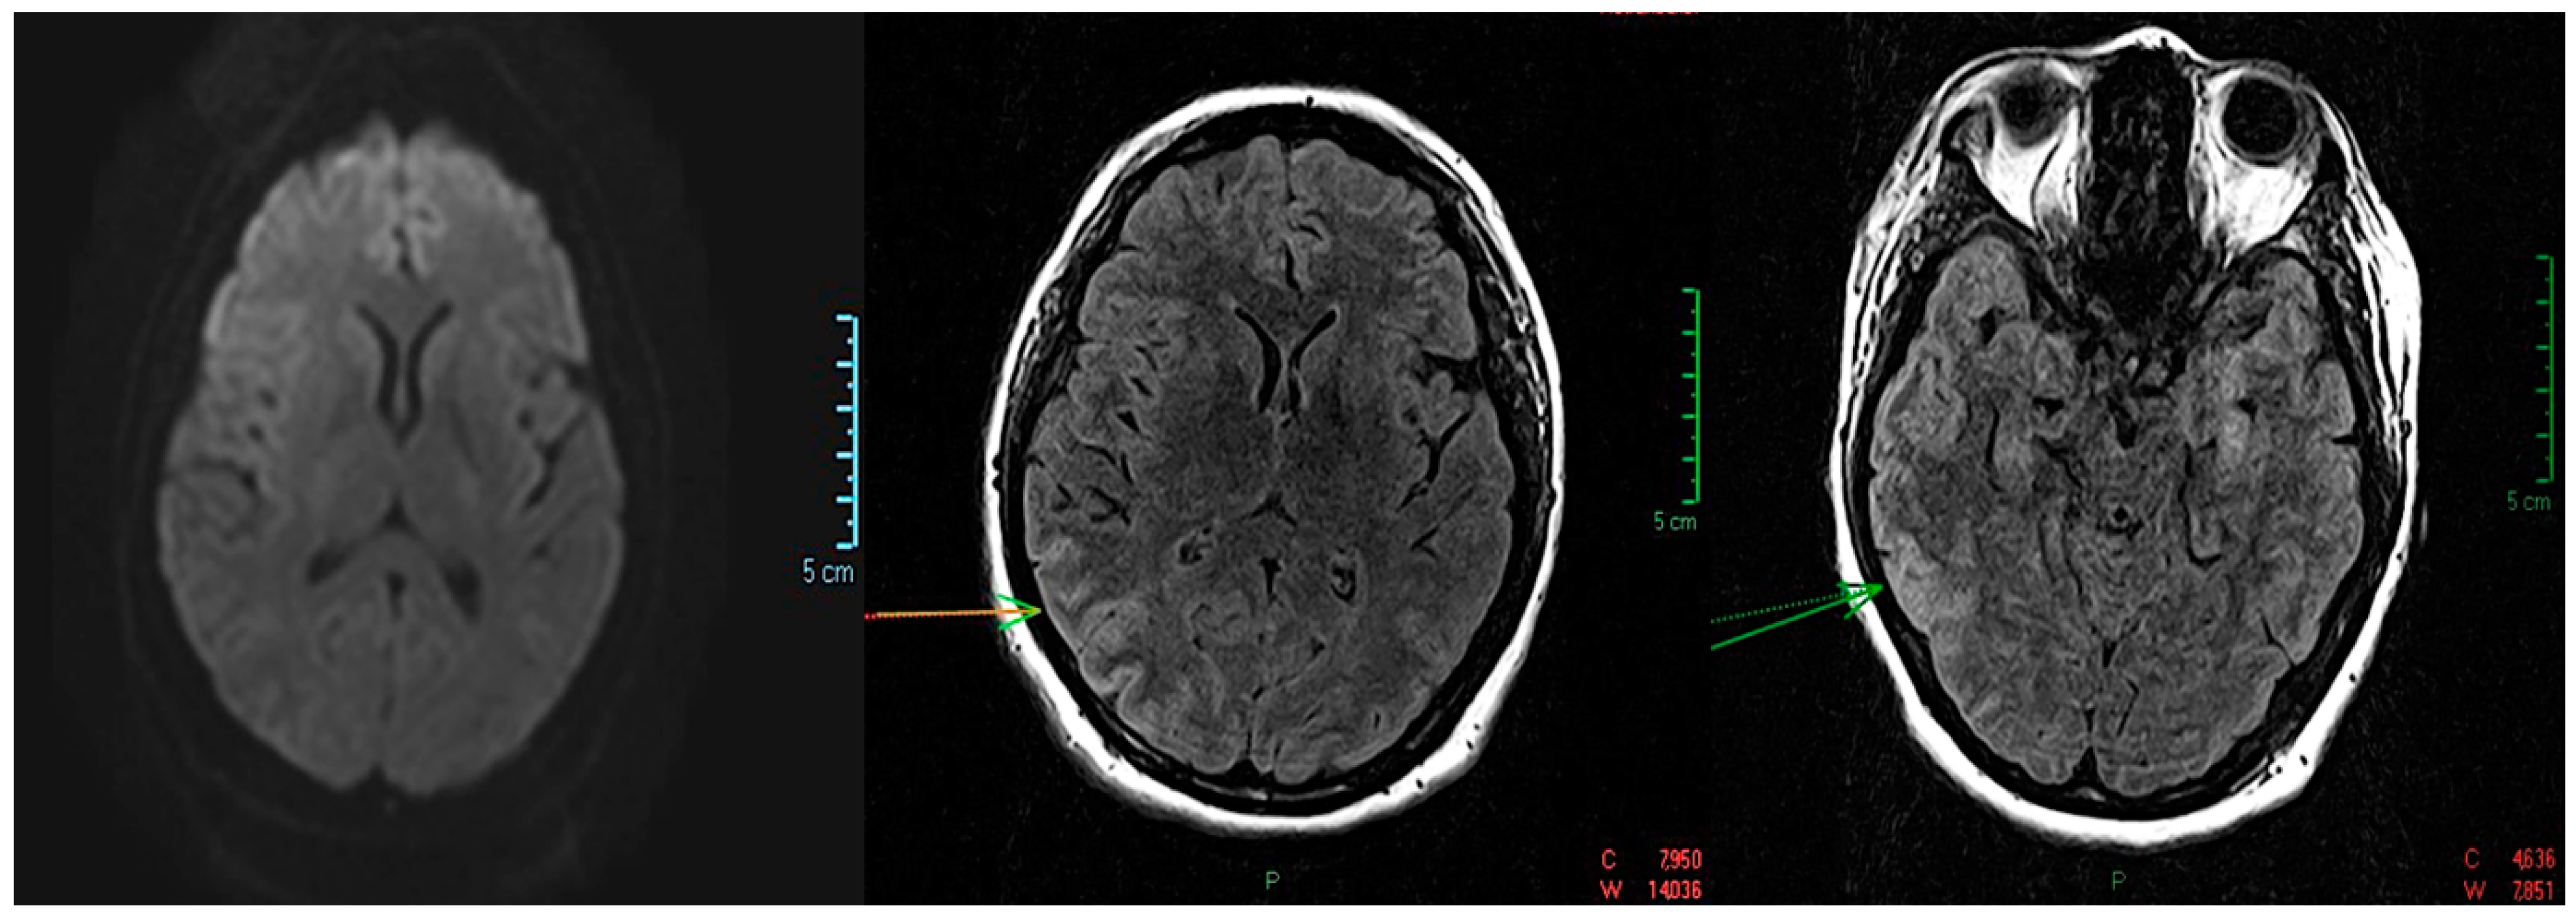

- a slight regression in the size and intensity of the T2 and FLAIR hyper signal, without restrictions on the diffusion sequence, not capturing the right temporo-occipital, associating a “swollen” aspect of the cortex with a slight erasure of the intergyral grooves, but without a mass effect on median line structures;

- small non-specific demyelinating lesions in hyper signal T2 and FLAIR, 2–4 mm, without diffusion sequence restriction, non-capturing, located in the frontoparietal subcortical and bilateral periventricular;

- no restrictions on the diffusion sequence, no hemorrhagic stigmata visible on the T2* sequence, no pathological intra/extra neuraxial contrast uptake or at the leptomeningeal level;

- normally positioned and sized ventricular system.